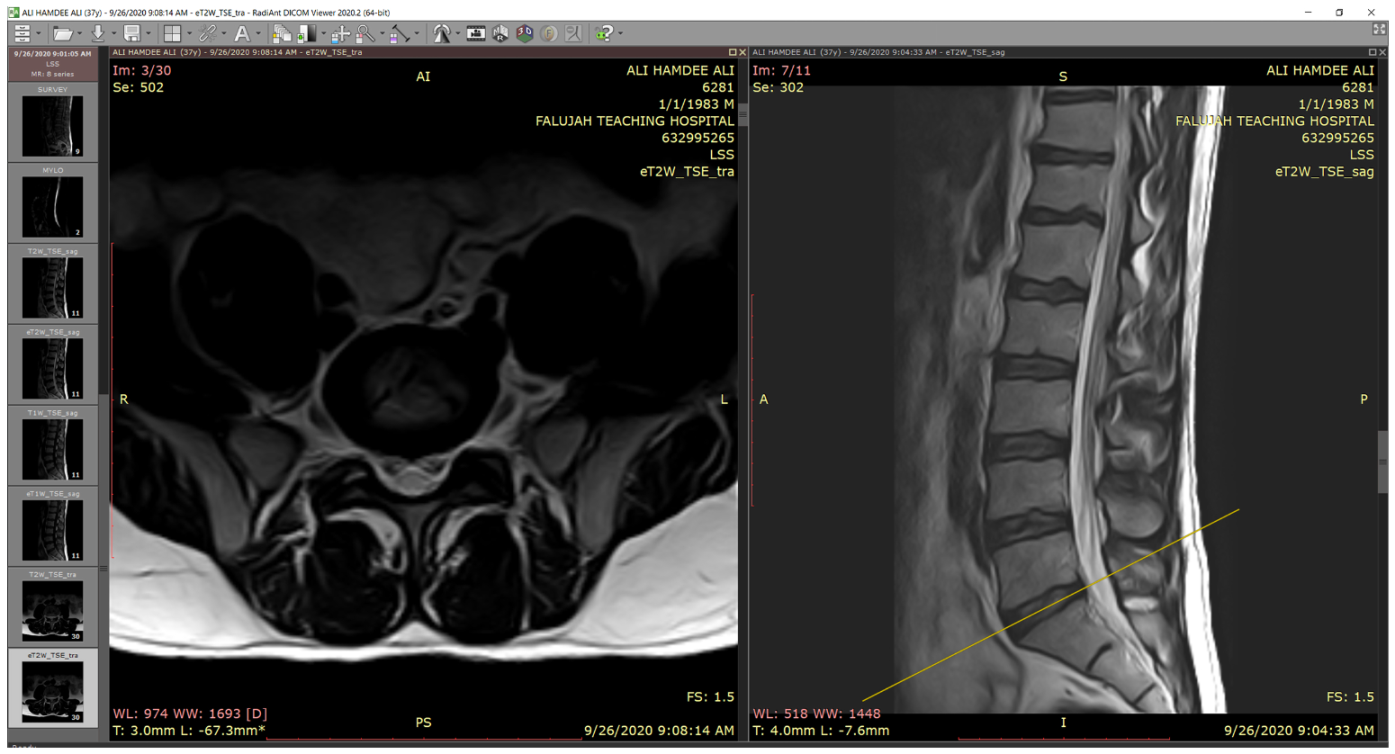

The classification was conducted by using the Fatima Label (FaLa) program. We created the FaLa program to help radiologists perform the labeling process with the help of RadiAnt [40] PACS DICOM viewer. Finally, the patient’s images are displayed on computers (see Figure 2).

As we note in Figure 2, there are several lumbar spine MRI series for each patient, such as survey, Mylo, sagittal T1, sagittal T2, axial T1, axial T2, and so forth. For each series, there are many images, for example, in Axial T2, we have 30 images. So, we are likely to receive 115 DICOMs per patient. In the diagnostic process, radiologists are interested in three series: myelography, axial T2, and sagittal T2.

Figure 2. RadiAnt DICOM viewer.